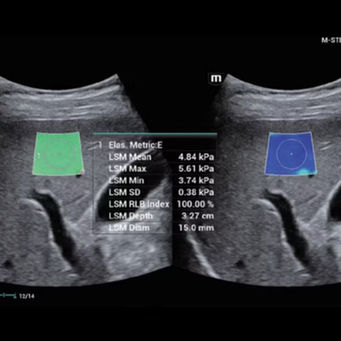

Innovative Steifigkeitsbewertung: HiFR STE von Leberfibrose & Quatifizierung mit HiFR STQ